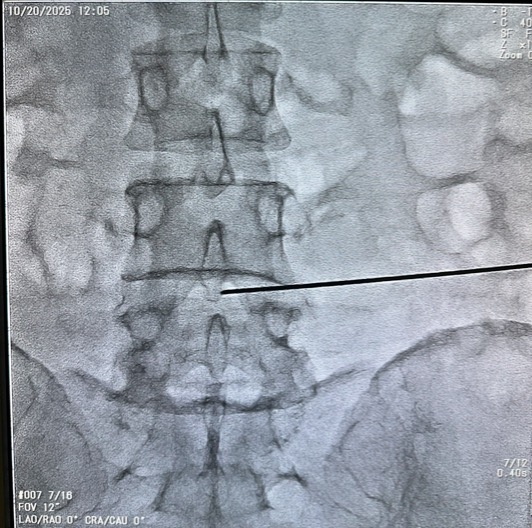

穿刺定位

:医生通过 C 型臂 X 光机或 CT 引导,将射频穿刺针精准刺入突出的髓核内部。这一步是手术的关键,影像引导可确保穿刺针不损伤神经和血管,患者此时可能会感到腰部有轻微酸胀感,但需保持身体不动,配合医生操作。